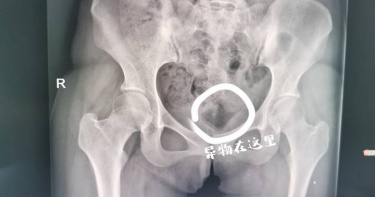

這種醫療疏失真離譜!印度一位30歲女子在剖腹產後身體不適,她以為自己得了腎結石或某種癌症,沒想到手術鉗殘留在她體內5年,經手術取出後,她氣到向當年的私立醫院提告。據《鏡報》報導,女子哈西尼亞(Harshinia)2017年在科澤科德醫院生下第3胎,之前她在當地的私立醫院進行了2次剖腹產,第3次剖腹產後,她開始感到劇烈疼痛。哈西尼亞說,「我找了很多醫師,我以為自己得了腎結石或某種癌症。」她甚至痛到要吃強效抗生素,而最近6個月中她又前往就醫。哈西尼亞表示,醫師幫她做了電腦斷層掃描,發現她的胃裡有個「金屬物體」。醫師說,金屬物體已經戳到哈西尼亞的膀胱,導致尿道感染。經過手術後手術鉗順利取出,哈西尼亞住院幾天後順利康復。科澤科德醫院說,「初步調查結果發現,本院的手術器械沒有弄丟,而這名女子之前在私立醫院做過2次手術。」目前哈西尼亞已對事發私立醫院提告;這案件同樣引起社會譁然,喀拉拉邦衛生部長表示,當局將對該醫院採取最嚴厲的制裁。此外,印度也有一位32歲男子因為肚子痛就醫,醫師發現他的胃裡有63 支湯匙。院方起初認為,男子的疼痛應該是腫瘤引起,可是掃描過後發現一團異物,經過外科醫師的2個小時的努力,才清完男子胃裡的所有湯匙。